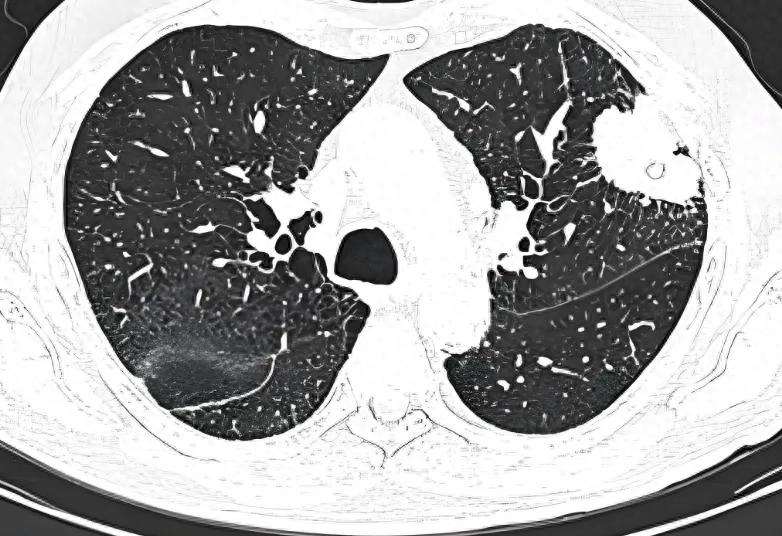

影像学检查:术后前 2 年每 3-6 个月行胸部 CT,之后每 6-12 个月一次,结合 PET-CT 排查转移。